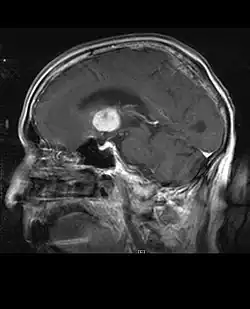

La tomodensitométrie (TDM) et L'imagerie par résonance magnétique (IRM) peuvent détecter efficacement une néoplasie dans le cerveau. L'IRM est plus sensible que la TDM pour identifier les lésions, mais présente des contre- indications pour les patients porteurs de stimulateurs cardiaques, de prothèses incompatibles, de clips métalliques et contre-indications. La TDM reste la méthode de choix pour détecter les calcifications au sein des lésions ou les érosions osseuses de la calotte ou de base du crâne. L'utilisation d' agents de contraste, iodés dans le cas du scanner et paramagnétiques (gadolinium) dans le cas de l'IRM, permet l'acquisition d'informations sur la vascularisation et l'intégrité de la barrière hémato-encéphalique, une meilleure définition de la tumeur tumorale par rapport à l' œdème environnant et à la génération d' hypothèses sur le degré de malignité. L'examen radiologique permet également d'évaluer les effets mécaniques et les modifications importantes des structures cérébrales résultant de la tumeur, telles que l' hydrocéphalie et les hernies, dont les effets peuvent être fatals. Enfin, en préparation à la chirurgie, ce diagnostic peut être utilisé pour déterminer la localisation de la lésion ou l'infiltration de la tumeur dans des zones vitales du cerveau. À cette fin, l'IRM est plus efficace que la tomodensitométrie car elle peut fournir des images en trois dimensions.

La tomodensitométrie du cerveau montre généralement une masse tissulaire qui peut être améliorée par l'un ou l'autre contraste. Au scanner, les gliomes de bas grade apparaissent généralement isodenses au parenchyme normal et peuvent donc ne pas présenter de rehaussement de contraste. De même, les lésions de la fosse crânienne postérieure sont difficiles à identifier au scanner. Par conséquent, les seuls résultats d'une telle tomographie ne sont pas toujours suffisants à des fins diagnostiques. Dans les cas douteux, l'utilisation de l'imagerie par résonance magnétique plus sensible est indispensable.

Sur-L'IRM montre une tumeur intracrânienne comme une lésion massive qui peut devenir plus luminescente après utilisation du produit de contraste. Cependant, il y a toujours une anomalie de signal dans -L'imagerie par résonance magnétique, qui indique la présence d'une néoplasie ou d'un œdème vasogénique. Habituellement, une luminescence accrue (amélioration du contraste) indique une tumeur d'un grade supérieur de malignité. Un anneau de contraste est caractéristique du glioblastome, avec la partie luminescente correspondant à la partie vitale de la tumeur maligne, et la plus foncée - zone hypointense correspondant à une nécrose tissulaire.

En règle générale, les patients atteints d'astrocytome anaplasique présentent des crises d'épilepsie, des déficits neurologiques focaux, des maux de tête et des changements de personnalité. L'âge moyen des patients est de 45 ans. L'imagerie par résonance magnétique montre généralement une lésion massive avec un signal de contraste accru, qui peut aussi être plus faible. Le diagnostic repose sur l'examen histologique de la lésion par biopsie ou résection chirurgicale.